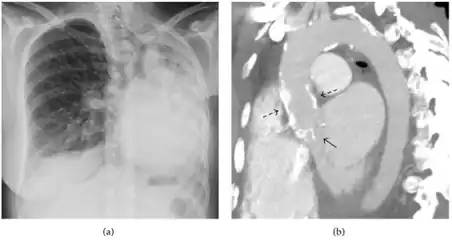

| Fibrothorax as seen on the left side of a chest x-ray (person's right side) | |

A fibrothorax can typically be diagnosed by taking an appropriate medical history in combination with the use of appropriate imaging techniques such as a plain chest X-ray or CT scan.[1] These imaging techniques can detect fibrothorax and pleural thickening that surround the lungs.[11] The presence of a thickened peel with or without calcification are common features of fibrothorax when imaged.[1] CT scans can more readily differentiate whether pleural thickening is due to extra fat deposition or true pleural thickening than X-rays.[1]

If a fibrothorax is severe, the thickening may restrict the lung on the affected side causing a loss of lung volume.[11] Additionally, the mediastinum may be physically shifted toward the affected side.[1] A reduction in the size of one side of the chest (hemithorax) on an X-ray or CT scan of the chest suggests chronic scarring.[9] Signs of the underlying disease causing the fibrothorax are also occasionally seen on the X-ray.[9] A CT scan may show features similar to those seen on a plain X-ray.[11] Lung function testing typically demonstrates findings consistent with restrictive lung disease.[9]